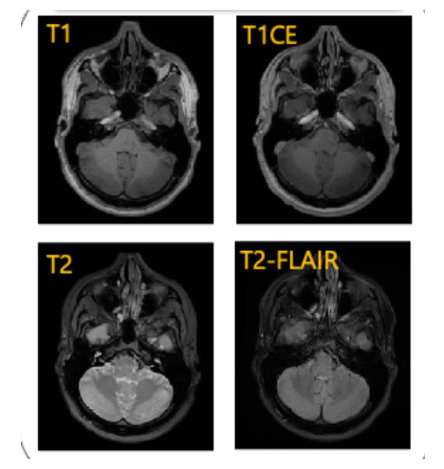

Pediatric brain tumors, particularly gliomas, represent a significant cause of cancer related mortality in children with complex infiltrative growth patterns that complicate treatment. Early, accurate segmentation of these tumors in neuroimaging data is crucial for effective diagnosis and intervention planning. This study presents a novel 3D UNet architecture with a spatial attention mechanism tailored for automated segmentation of pediatric gliomas. Using the BraTS pediatric glioma dataset with multiparametric MRI data, the proposed model captures multi-scale features and selectively attends to tumor relevant regions, enhancing segmentation precision and reducing interference from surrounding tissue. The model's performance is quantitatively evaluated using the Dice similarity coefficient and HD95, demonstrating improved delineation of complex glioma structured. This approach offers a promising advancement in automating pediatric glioma segmentation, with the potential to improve clinical decision making and outcomes.